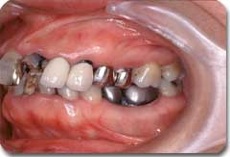

かみ合わせ治療前の状態です

かみ合わせ治療によりここまで治すことができます